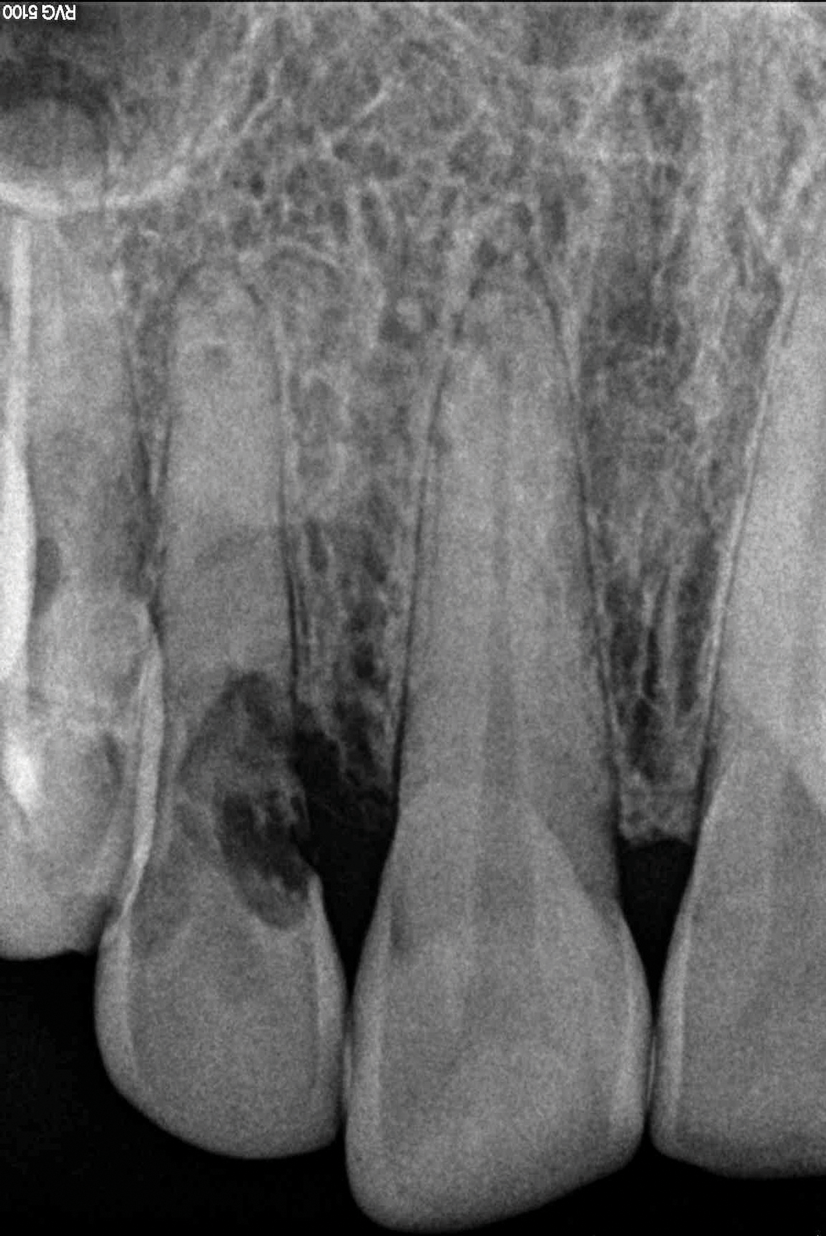

(2.) Close-up right lateral view of the tooth No. 7 site following extraction and implant placement.

Figure 2

Depending on whether patients present with an existing edentulous space or a non-restorable tooth requiring extraction, as well as other factors, their long-term treatment goals may vary. Nonetheless, each case should be evaluated to identify patients' needs regarding immediate restoration. In the example case presented here, a radiographic examination of a discolored canine lead to the discovery of a lateral incisor (tooth No. 7) with internal resorption that required extraction (Figure 1). The tooth was extracted, and an implant was subsequently placed (Figure 2); however, the patient would be unable to complete the treatment for an extended period of time, so a fiber-reinforced composite bridge was chosen to serve as an ideal long-term provisional replacement option.